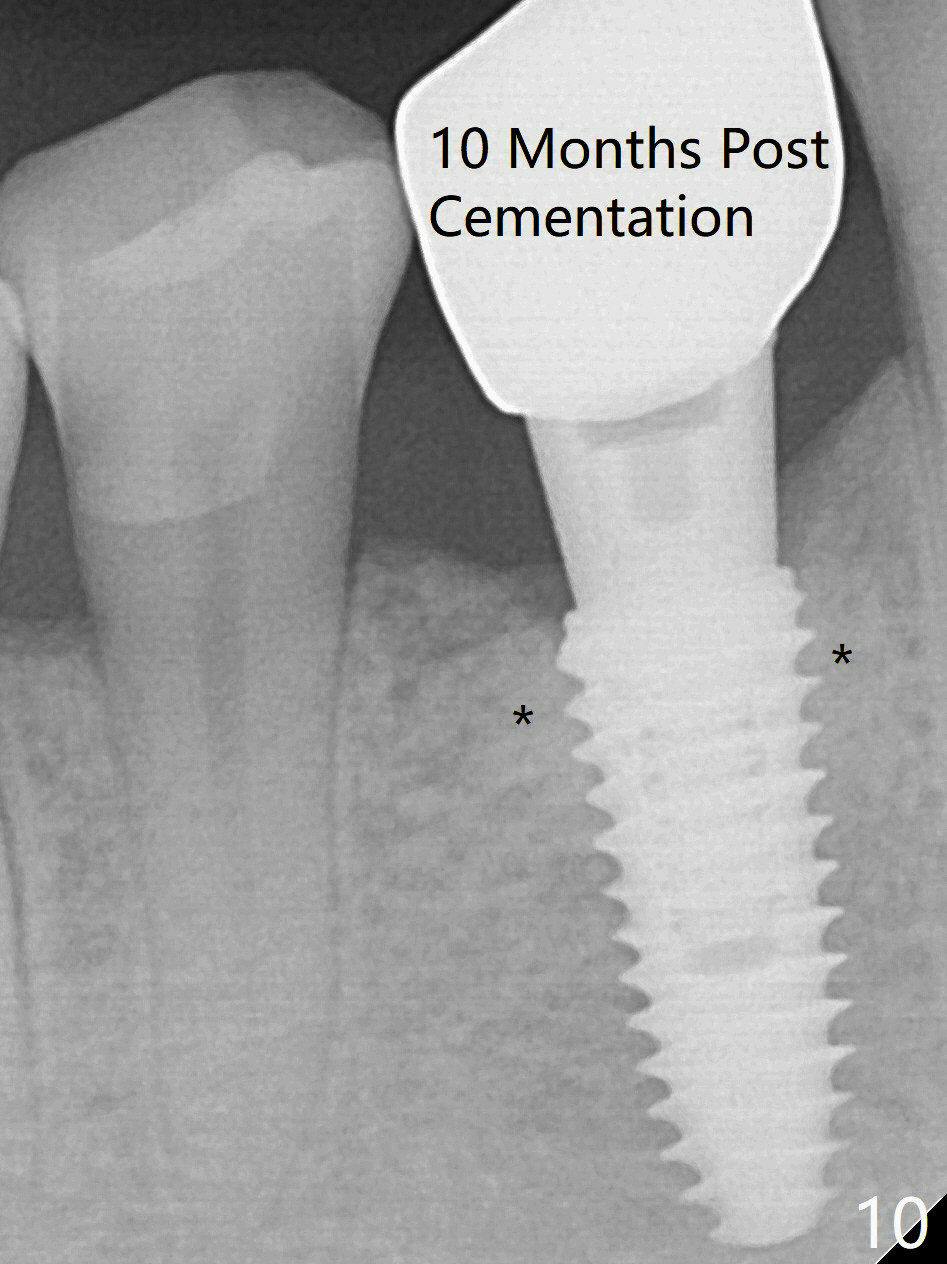

Immediately post extraction and curettage of the large buccal apical lesion, osteotomy is established in the lingual wall of the socket of #28 (slightly distal) for 17 mm vs. 15 mm socket depth (Fig.1 (red line: Mental Loop)). Following sequential osteotomy until 3.5x17 mm drill, a 4x10 mm dummy implant is partially placed with stability (Fig.2,3 (root measurement: mesiodistal 4 mm; buccolingual 7 mm)). A final implant (4x11.5 mm) is placed with insertion torque of 60 Ncm (Fig.4,5). Since the buccal crest is lower with the buccal gingival recession, the implant is intentionally placed deep as well as lingually so that autogenous bone and Vera graft mixture will be placed in the buccal gap (Fig.6 * (gauze at the moment)). The apical lesion decreases 4.5 months postop (Fig.7). Immediate implant and immediate provisional keep the papillae (Fig.8 *), but cannot prevent the buccal plate from atrophy (Fig.9 *). It appears that socket shield is able to accomplish the latter. The bone density next to the coronal threads increases 10 months post cementation (Fig.10 *) and seems to have continued to do so 1 year 4 months post cementation (Fig.11).